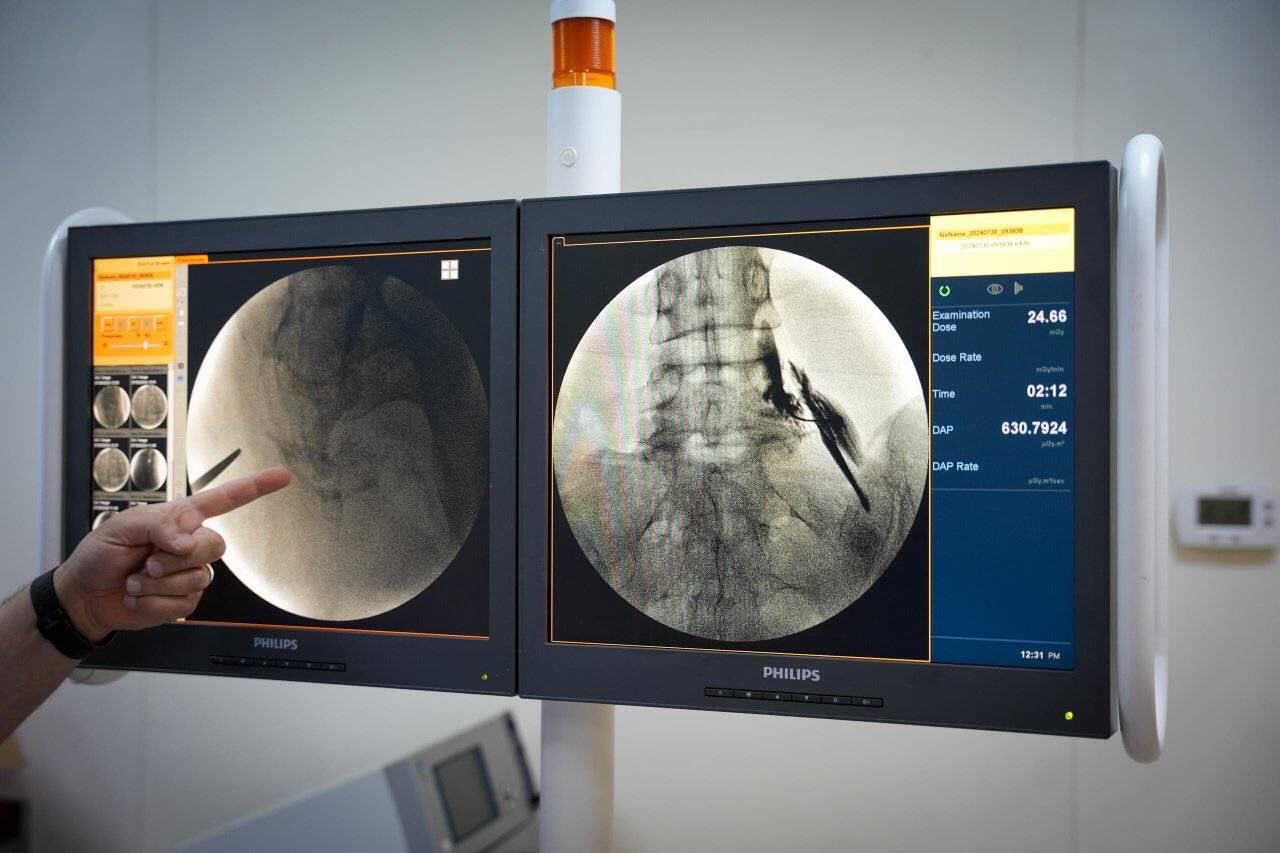

استقبلت وحدة علاج الألم بمستشفى الجلاء للجراحة والحوادث بنغازي، أمس الإثنين، 30 حالة جديدة، وفي اليوم التالي، الثلاثاء، تم إجراء عمليات حقن الألم لـ9 حالات، حيث تم حقن المرضى في أماكن مختلفة من الجسم حسب الحاجة وتبعًا لموضع الألم. وقد تمت عمليات الحقن تحت إشراف استشاري العمود الفقري وجراحة العظام والمفاصل، د. خالد اعنيبة، بالتعاون مع د. سراج الجهاني ود. أميرة المستيري، بالإضافة إلى نخبة من الأطقم الطبية المتميزة بمستشفى الجلاء. والجدير بالذكر أن د. اعنيبة متواجد بوحدة علاج الألم خلال زيارته للمستشفى، والتي ستستمر لمدة أربعة أيام من يوم 29 يوليو حتى 01 أغسطس. يأتي هذا الجهد في إطار سعي المستشفى لتقديم أفضل رعاية صحية للمرضى وتخفيف آلامهم باستخدام أحدث التقنيات العلاجية.